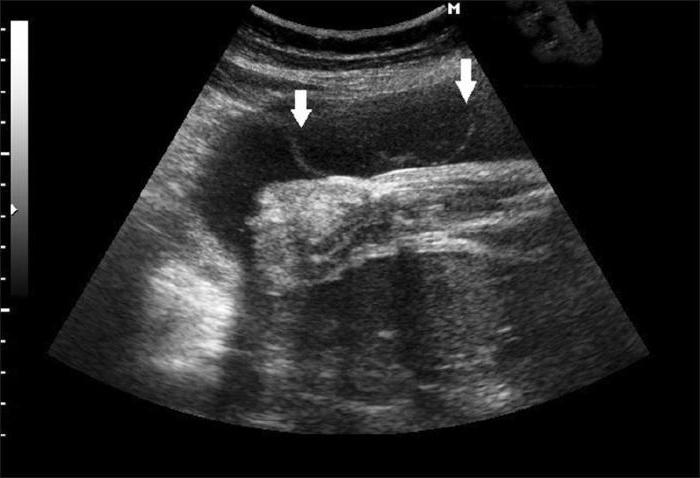

- Ультразвуковое исследование – является наиболее безопасным и безболезненным методом;

- УЗИ – самый простой и безопасный тест на околоплодные воды, который позволяет обнаружить взвеси в амниотической жидкости.

Характер околоплодных вод играет важное значение в диагностике осложнений в период беременности. Нередко будущая мама во время ультразвукового исследования узнает о наличии взвеси в водах при беременности, что несомненно, пугает и настораживает не только саму женщину, но и врача. Что делать в такой ситуации, и насколько серьезным считается появление примеси в амниотической жидкости?

Если с матерью и ребенком в течение гестационного срока было все хорошо, то при излитии во время родов амниотическая жидкость будет бесцветной, прозрачной или слегка мутноватой за счет содержания в ней чешуек эпидермиса, пушковых волосков и смазки плода – свободно плавающих частичек, или взвеси.

Взвесь в водах при беременности может указывать на кислородное голодание ребенка, при котором в жидкости появляются частички мекония, а также признаком внутриутробного инфицирования, что также приводит к помутнению.

ВАЖНО! Взвесь в околоплодных водах при отсутствии других клинических симптомов является вариантом нормы и не требует лечения.

Несмотря на все преимущества ультразвуковой диагностики, данный метод позволяет лишь установить факт наличия примеси в амниотической жидкости, однако не дает никаких объяснений по поводу причин ее возникновения. Если того требует тактика ведения беременности, врач принимает решение о дополнительном исследовании околоплодных вод с помощью таких методов, как амниоскопия и амниоцентез.

Следует учитывать, что появление примесей в амниотической жидкости в период беременности по данным УЗИ – это не диагноз, а всего лишь повод для тщательного обследования.

- Ультразвуковая диагностика;

Чаще каждого назначается УЗИ. Профилактические осмотры разрешают выявить отклонения на самых ранних стадиях. Помимо того, данный вид изыскания является дюже информативным. Стоит подметить, если при УЗИ найдена эхогенная взвесь у женщины в околоплодных водах, но при этом состояние плода и матери является типичным, то данное состояние не является тревожным знаком.

Например, ультразвуковое обследование покажет, что имеется гиперэхогенная взвесь в определенном в околоплодных водах, но не будет видно, меконий это либо нет.